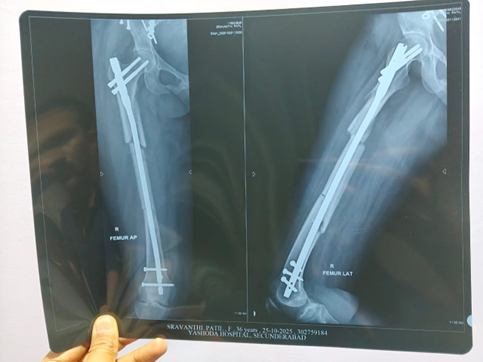

Follow-Up and Outcome. After the commencement of Homoeopathic treatment, gradual improvement was noted. Wound healing progressed satisfactorily. Radiological evidence showed bony callus formation and improved union. Gastric complaints subsided completely. The patient returned to normal mobility and daily activities.

During Treatment